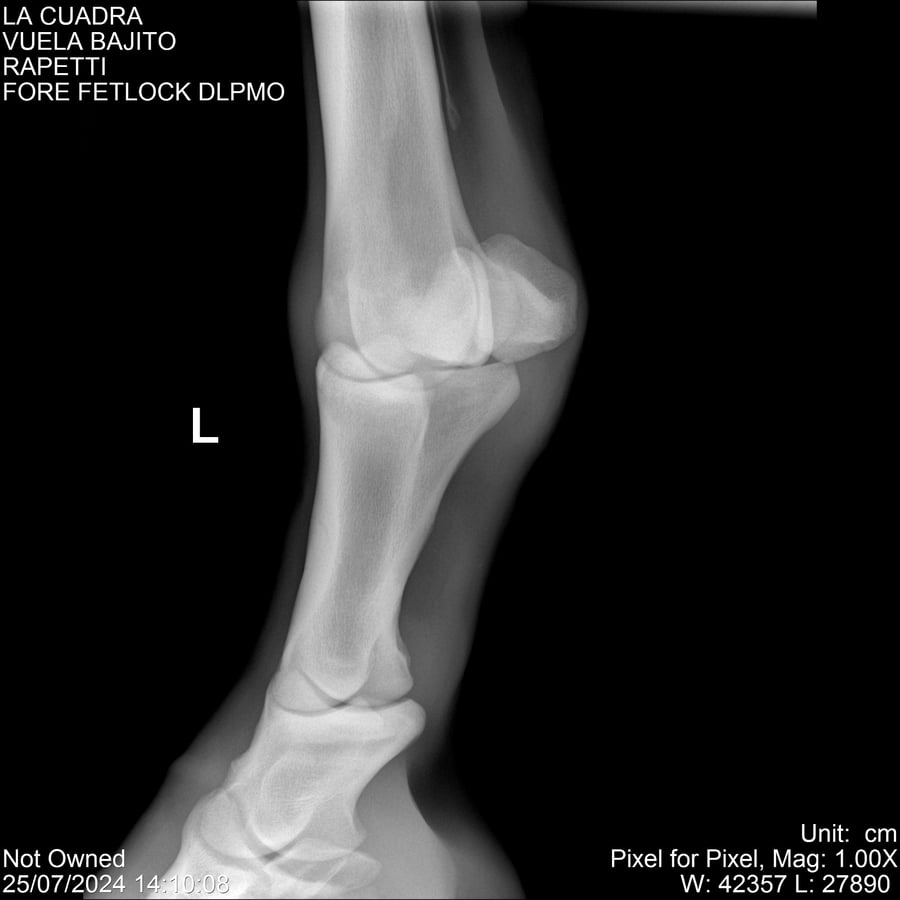

LOTE 16, VUELA BAJITO Lote Anterior Volver al remate Lote Siguiente Ficha Contacto Montevideo - Ficha del Lote Identificador: #284451 Categoría: Yeguarizos Montevideo - 77 Visualizaciones ClicData Contacto Empresa: Abelenda N. R., Walter Hugo Nombre*: Teléfono* : E-mail* : Mensaje Enviar Registrese gratis Este contenido Exclusivo está disponible sólo para usuarios registrados Ingresar